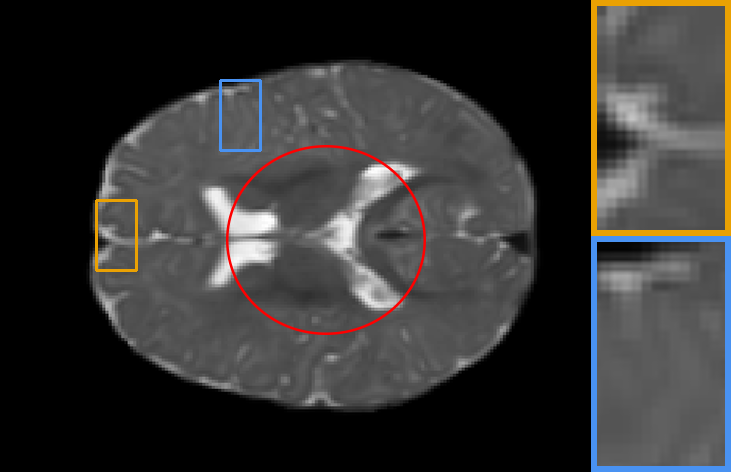

| Brain T1-to-T1 | Brain T2-to-T2 | Knee T1-to-T1 | Brain T2-to-T1 |

IV-C2 Automatic learning across registration tasks

To explore the influence of model weights, architectures, and training objectives in registration performance and verify the benefit from adaptive feature extraction cell, task-aware deformation estimation cell design, and scenario-oriented training objectives, we made groups of contrast experiments, covering diverse registration scenarios. Specifically, we first train a registration model on PPMI brain T1 MR image-to-atlas registration tasks, then take the model as initialization to adopt our auto-search strategy to register images of other different scenarios. The scenarios cover registration on another ADNI dataset, Brain T1-to-T1, Brain T2-to-T2, Knee T1-to-T1 and Brain T2-to-T1 setups.

In Table. II, we directly apply the model (with , , and ) on the PPMI dataset to other scenarios, corresponding to the 1st column result, showing poor performance. Whereas performances of re-trained models (with task-specific model weight ) on these tasks correspond to the 2nd column. We also demonstrate the performance of searched networks with auto-learned feature cells , deformation cells , and training objectives , corresponding to the 3rd to 5th columns. To fully capture the benefit of the proposed technique, we further report the increase in registration accuracy for cases where all hyperparameters are searched in the last column. We can observe that, firstly, retraining the model for different alignment tasks will result in better performance. Secondly, searched tailored architecture and training objectives largely improve numerical results, which means automatic learning combining training objectives, architectures and hyperparameters can achieves excellent alignment performance in different alignment scenarios.

Also, the models on the diagonal with a blue background perform second best which can be seen from Table. II, providing meaningful indications and conclusions. Firstly, when transferring to another dataset or image contrast, feature extraction plays a dominant role in model performance. Secondly, whereas transferring to another anatomical structure such as the knee data, regulating the deformation estimation section has a more significant impact on the performance of the model. Lastly, adjusting the training objective plays a more important role in the performance of a registration network when transferring to multi-modal datasets.